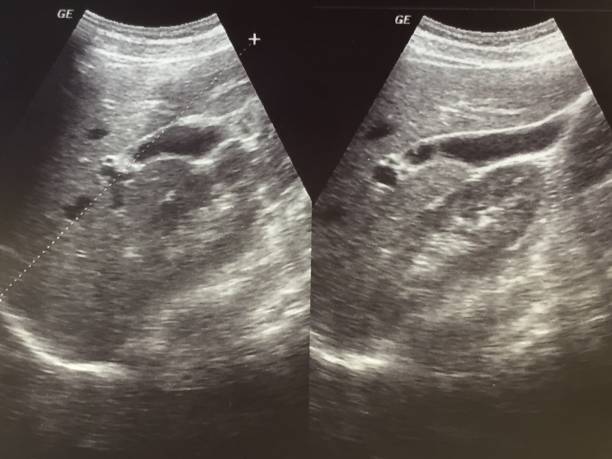

Ecografie a Roma per una diagnosi precoce e sicura

All’Aventino Medical Group, nel centro di Roma, l’ecografia è uno strumento chiave per individuare precocemente alterazioni di organi, tessuti e vasi sanguigni. Grazie a tecnologie di ultima generazione e a specialisti esperti, offriamo esami rapidi, accurati e non invasivi, per una valutazione tempestiva della tua salute e un percorso di cura personalizzato.

L’ecografia è un esame diagnostico fondamentale in molte specializzazioni mediche. Le principali applicazioni comprendono:

- Ecografia addominale: fegato, pancreas, reni, milza, vie biliari, intestino.

- Ecografia tiroidea: monitoraggio della tiroide e dei noduli.

- Ecografia pelvica e ginecologica: valutazione dell’apparato riproduttivo femminile.

- Ecografia muscolo-scheletrica: tendini, muscoli e legamenti.

- Ecocolordoppler vascolare: studio della circolazione venosa e arteriosa.